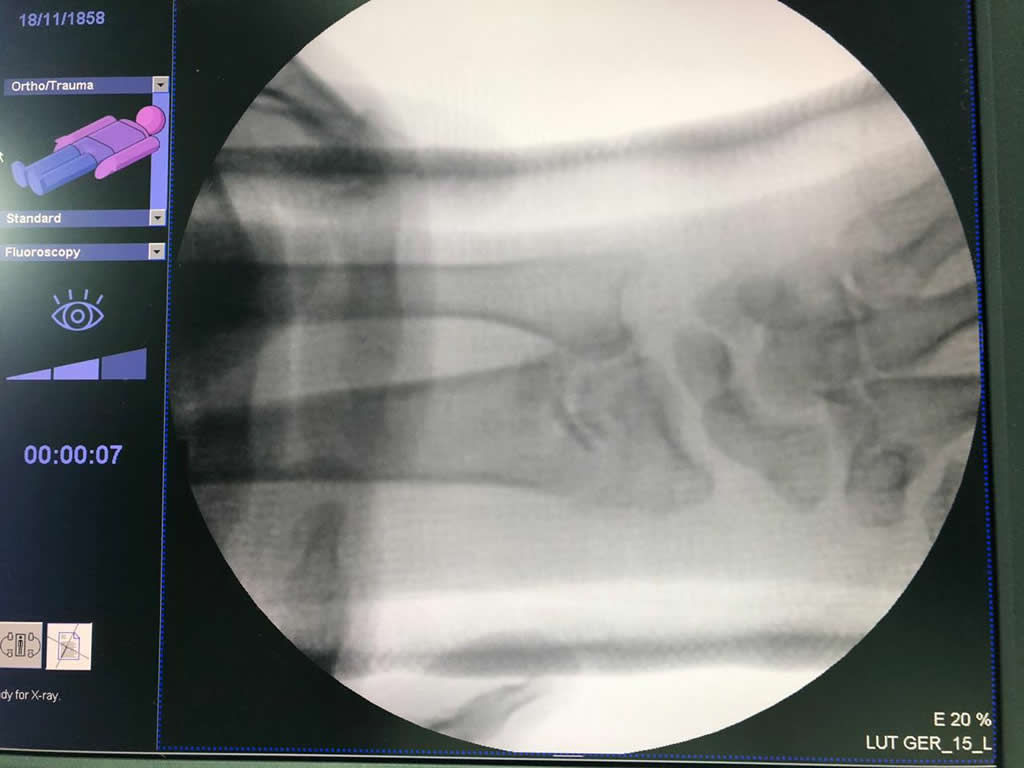

Cirugías de Muñecas

Los procedimientos más comunes en cirugía de la mano son aquellos destinados a reparar traumatismos, incluyendo lesiones de tendones, nervios, vasos sanguíneos, y articulaciones; huesos fracturados; y quemaduras, cortes, y otros daños de la piel.